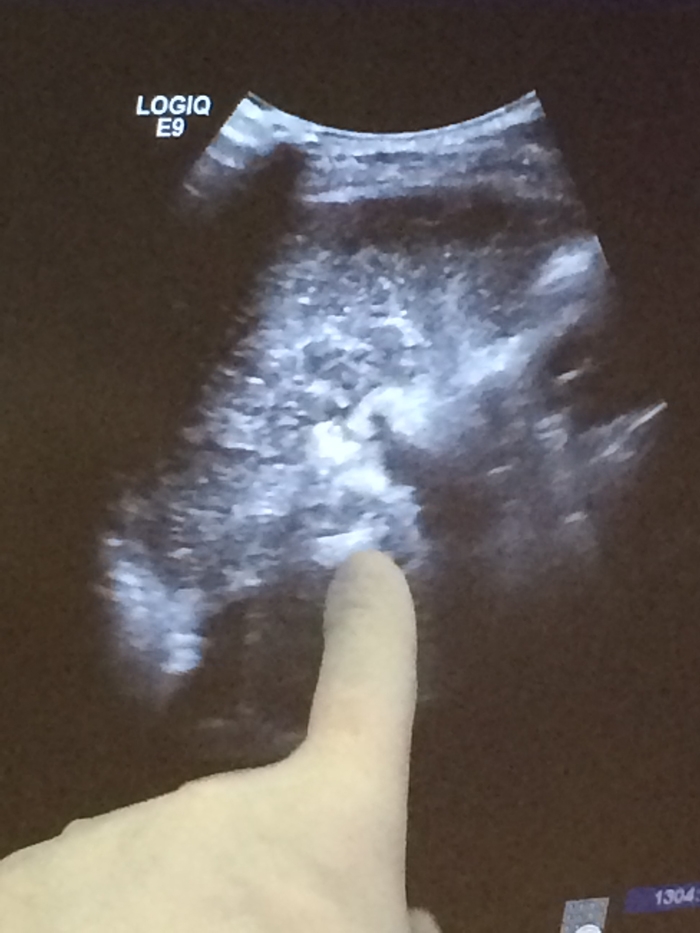

術(shù)中彩超定位尾狀葉腫塊

??? 近日,毛大爺接受了這項(xiàng)治療。在超聲引導(dǎo)下,由皮膚直接插入細(xì)針直達(dá)尾狀葉腫瘤瘤體,通過射頻能量徹底破壞腫瘤。治療過程不到半小時(shí),體表除了一個(gè)難辨的針眼外沒有留下任何疤痕。術(shù)后當(dāng)天就下床活動(dòng),第三天行動(dòng)自如。